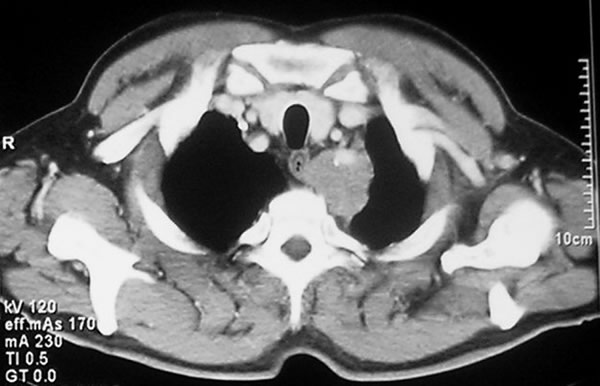

Рентгеновские снимки опухоли Панкоста